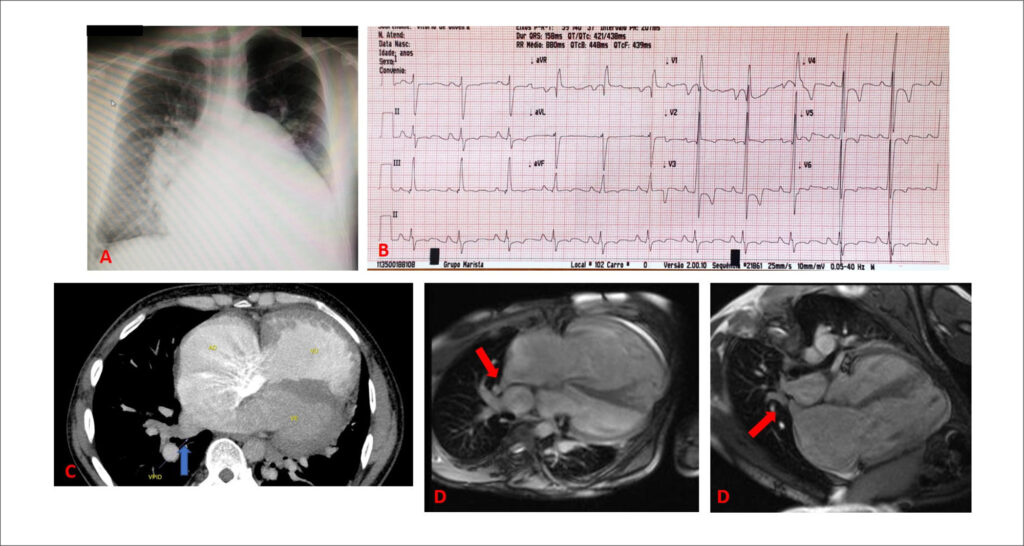

Heart Failure Due to Anomalous Pulmonary Vein Connection Associated with Atrial Septal Defect

Anomalous pulmonary vein dreinage (APVD) is a rare disease, accounting for nearly 1 to 3% of congenital heart diseases. It may be total, when all PVs are involved, or partial, when only some PVs drain anomalously into one or more systemic veins or directly into the right atrium (RA)., This condition occurs alone or in association with an interatrial septal defect, more often sinus venosus interatrial communication (IAC) (which accounts for nearly 5% of all IAC cases).

Patients with this condition may remain asymptomatic until adulthood. However, overload of right chambers may trigger symptoms, especially reduced functional capacity and progressive dyspnea, in addition to the development of pulmonary hypertension (PH) and ventricular dysfunction, which is the most severe disease scenario. Recognizing these symptoms and establishing early diagnosis and treatment is crucial to avoid disease progression and its prognostic implications.